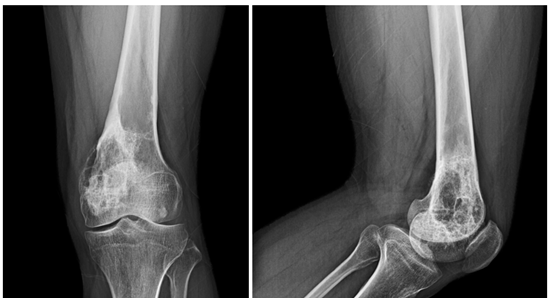

患者男性,36岁,7年前因左侧大腿疼痛就诊于外院,诊断为左股骨远端良性病变(骨纤维结构不良),7年内2次行肿瘤刮除+自体髂骨植骨术,术区骨质吸收,愈合不良。近1月来患者无诱因下左膝关节疼痛,活动后加剧,VAS评分4分,局部皮肤无发红,皮温正常